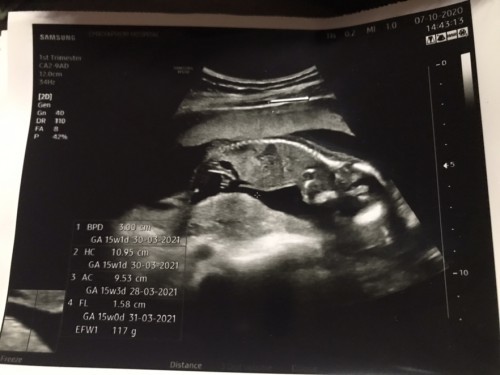

15wแล้ว🎉 จากเจ้าถั่วน้อยในวันนั้น กลายเป็นเบบี๋น้อยในวันนี้ วันนี้ได้ไปซาวด์มากหนูเป็นผู้หญิงชัดเจนค่า😅ไม่ปิดบังเลยไม่ได้ตังใจว่าจะไปดูเพศ แต่หนูให้ลุงหมอเห็นชัดเจนเลยแม่ไม่ต้องลุ้นเลยจ้า สมใจคุณพ่อเขาเลยแหละ อิหล่าน้อย😅👶🏻🎉

ตอนแรกไม่คิดว่าจะได้เห็นคิดว่าน่าจะ5เดือน ถึงจะเห็นชัด พอหมอซาวดูแปบเดี๋ยวหมอการันตีเลยว่าผู้หญิงชัดเจน หมอบอกนี่แคม2ข้างผู้หญิง 100% ครับ ไม่มีให้ลุ้นเลยค่า 😅